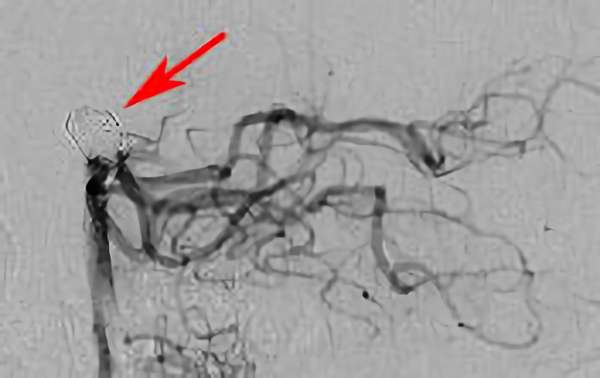

No.1631 手術後